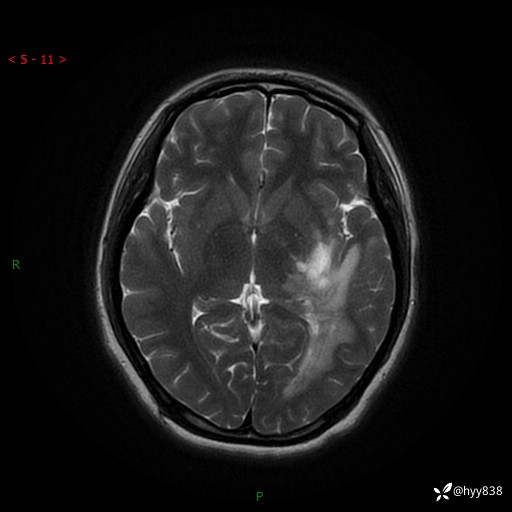

颅脑MRI平扫+增强